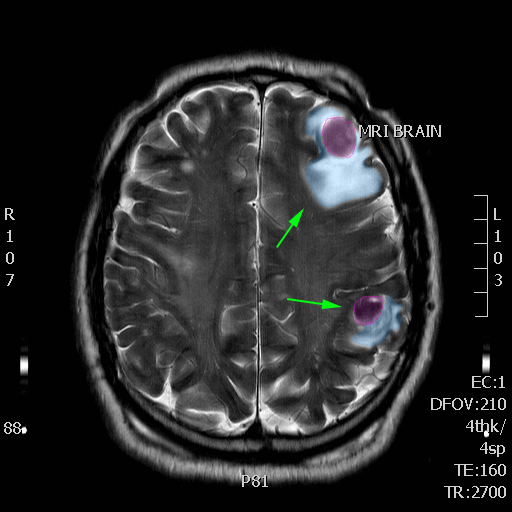

Πολλαπλές μεταστάσεις σε διάφορα σημεία του εγκεφάλου. |